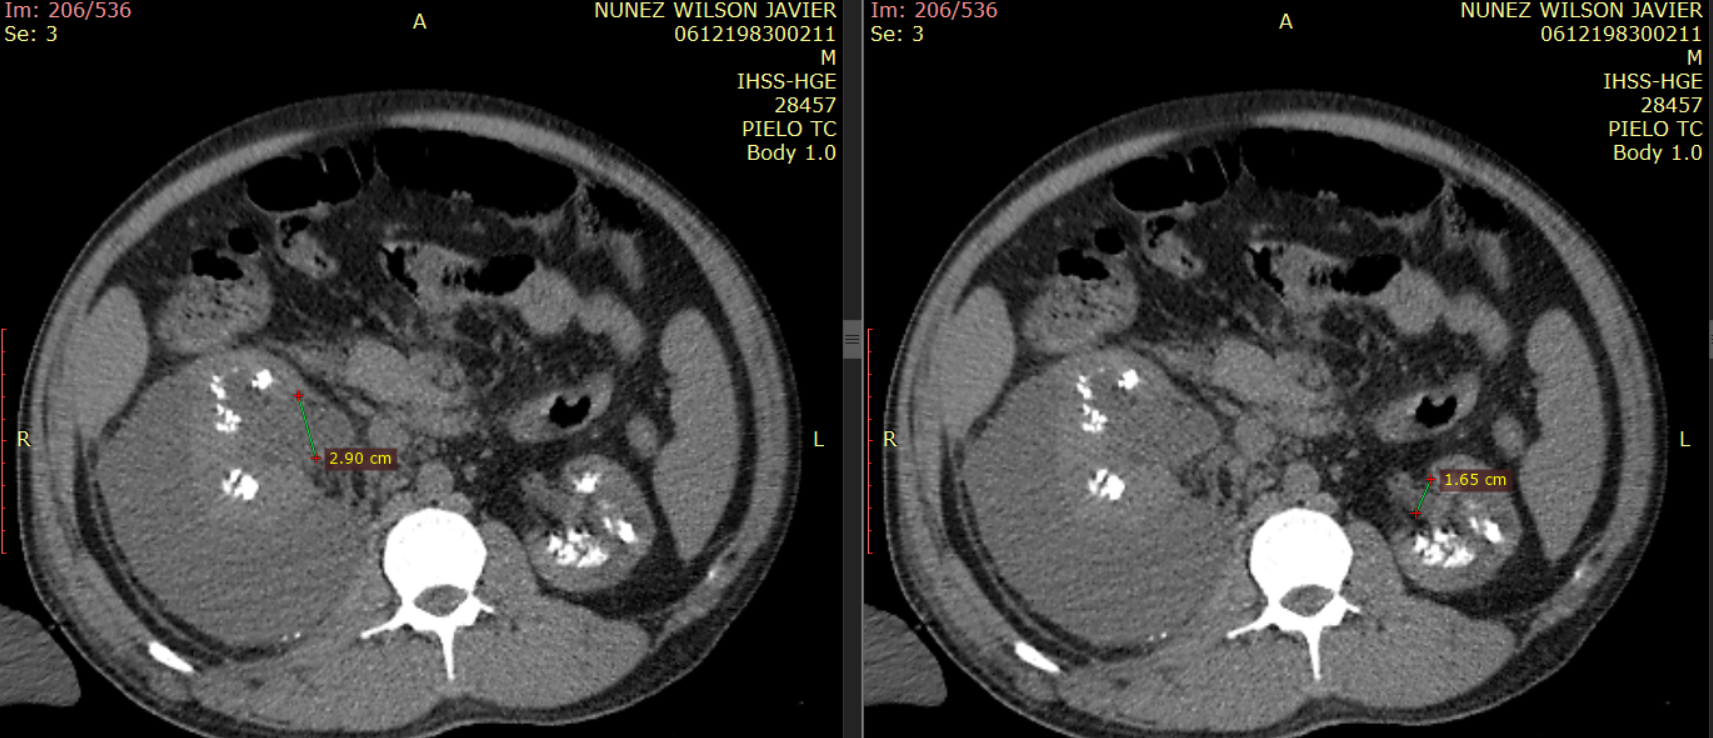

24 horas posterior a ingreso se ordena pielotomografía (no se realiza urotomografía por creatinina de 10mg/dl).

Imagen 6. Imagen de reconstrucción coronal de tomografía abdominal sin contraste (pielotomografia) donde se identifican imágenes hiperdensas en ambos riñones a nivel de pirámides renales, así mismo se observa la presencia de colección perirrenal derecha.

Ambos riñones se observan con presencia de imágenes hiperdensas en sitio anatómico de pirámides renales (valores de atenuación de hasta 1082UH) con presencia de colección perirrenal con densidad liquido (12UH) rodeando riñón derecho. Se observa estriación de la grasa en plano retroperitoneal derecho, extendiéndose hasta fosa iliaca derecha.

Imagen 10. Corte axial de tomografía abdominal sin contraste mostrando la presencia de imágenes hiperdensas en pirámides renales.

Imagen 10 y 11. Muestran cortes axiales a diferentes niveles demostrando la presencia de litos en tercio medio de ambos urteres.

Imagen 12 y 13. Magnificaciones de una tomografía abdominal sin contraste Demostrando la presencia de imágenes hiperdensas, dispuestas de forma difusa en pirámides renales,con presencia de colección perirrenal derecha, aumentado de tamaño.